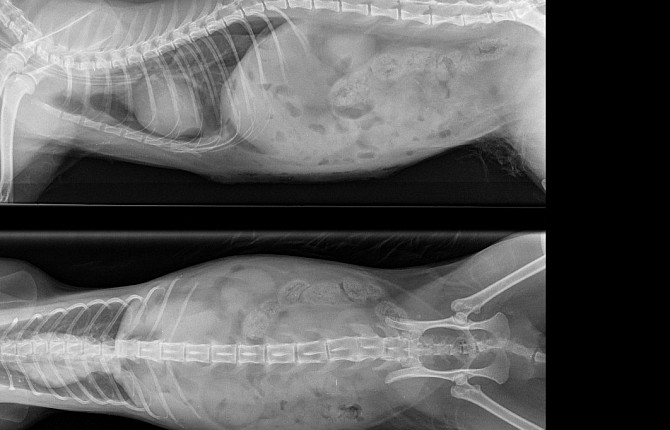

Рентгенографическое исследование грудной клетки является основным при постановке диагноза. Диафрагмальную грыжу у кошек и собак подозревают всегда, когда отсутствует четкая линия диафрагмы. Наличие органов брюшной полости в грудной полости подтверждает диагноз. Иногда наличие плеврального выпота затрудняет постановку диагноза, и требует проведение контрастных исследований.

Контрастная рентгенография верхних отделов ЖКТ подтверждает диагноз, если часть желудка или кишечника наблюдается в грудной полости.